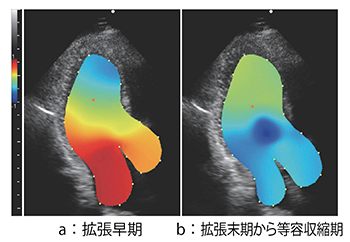

2.相対圧イメージング

断面内の速度分布情報から,ナビエストークスの方程式を用いて心腔内の相対圧分布(Relative Pressure Imaging:RPI)を推定している14)。

断層面内の相対圧表示例を示す(図6)。断層像の中心の赤い点が基準点を示し,その点より圧の低いところを青色系で,圧の高いところを赤色系で表示している。図6 aは拡張早期の時相で僧帽弁側に比べ心尖部側に圧力が低く,これはsuctionが生じていることを示している。図6 bは拡張末期から等容収縮期の時相において,左室中央部に発生する渦では圧が周囲より低圧になっていることを示している。拡張早期の時相では僧帽弁側に比べ心尖部側に圧力が低く,これは左室への能動的血流の吸引を表すsuctionが生じていることを示している。このRPIから推定した拡張早期左室内圧較差(IntraVentricular Pressure Gradient:IVPG)が,健常者と左室駆出率(LVEF)が保たれた心不全である拡張性心不全(HFpEF)患者の区別に応用できることを期待されている。

図6 相対圧表示